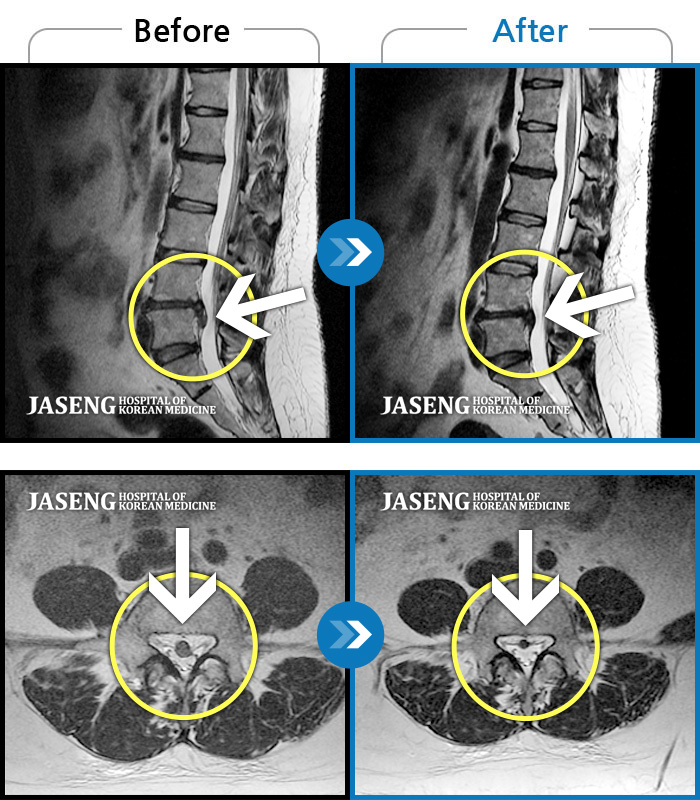

[뱸] 19.11.28~25.05.06